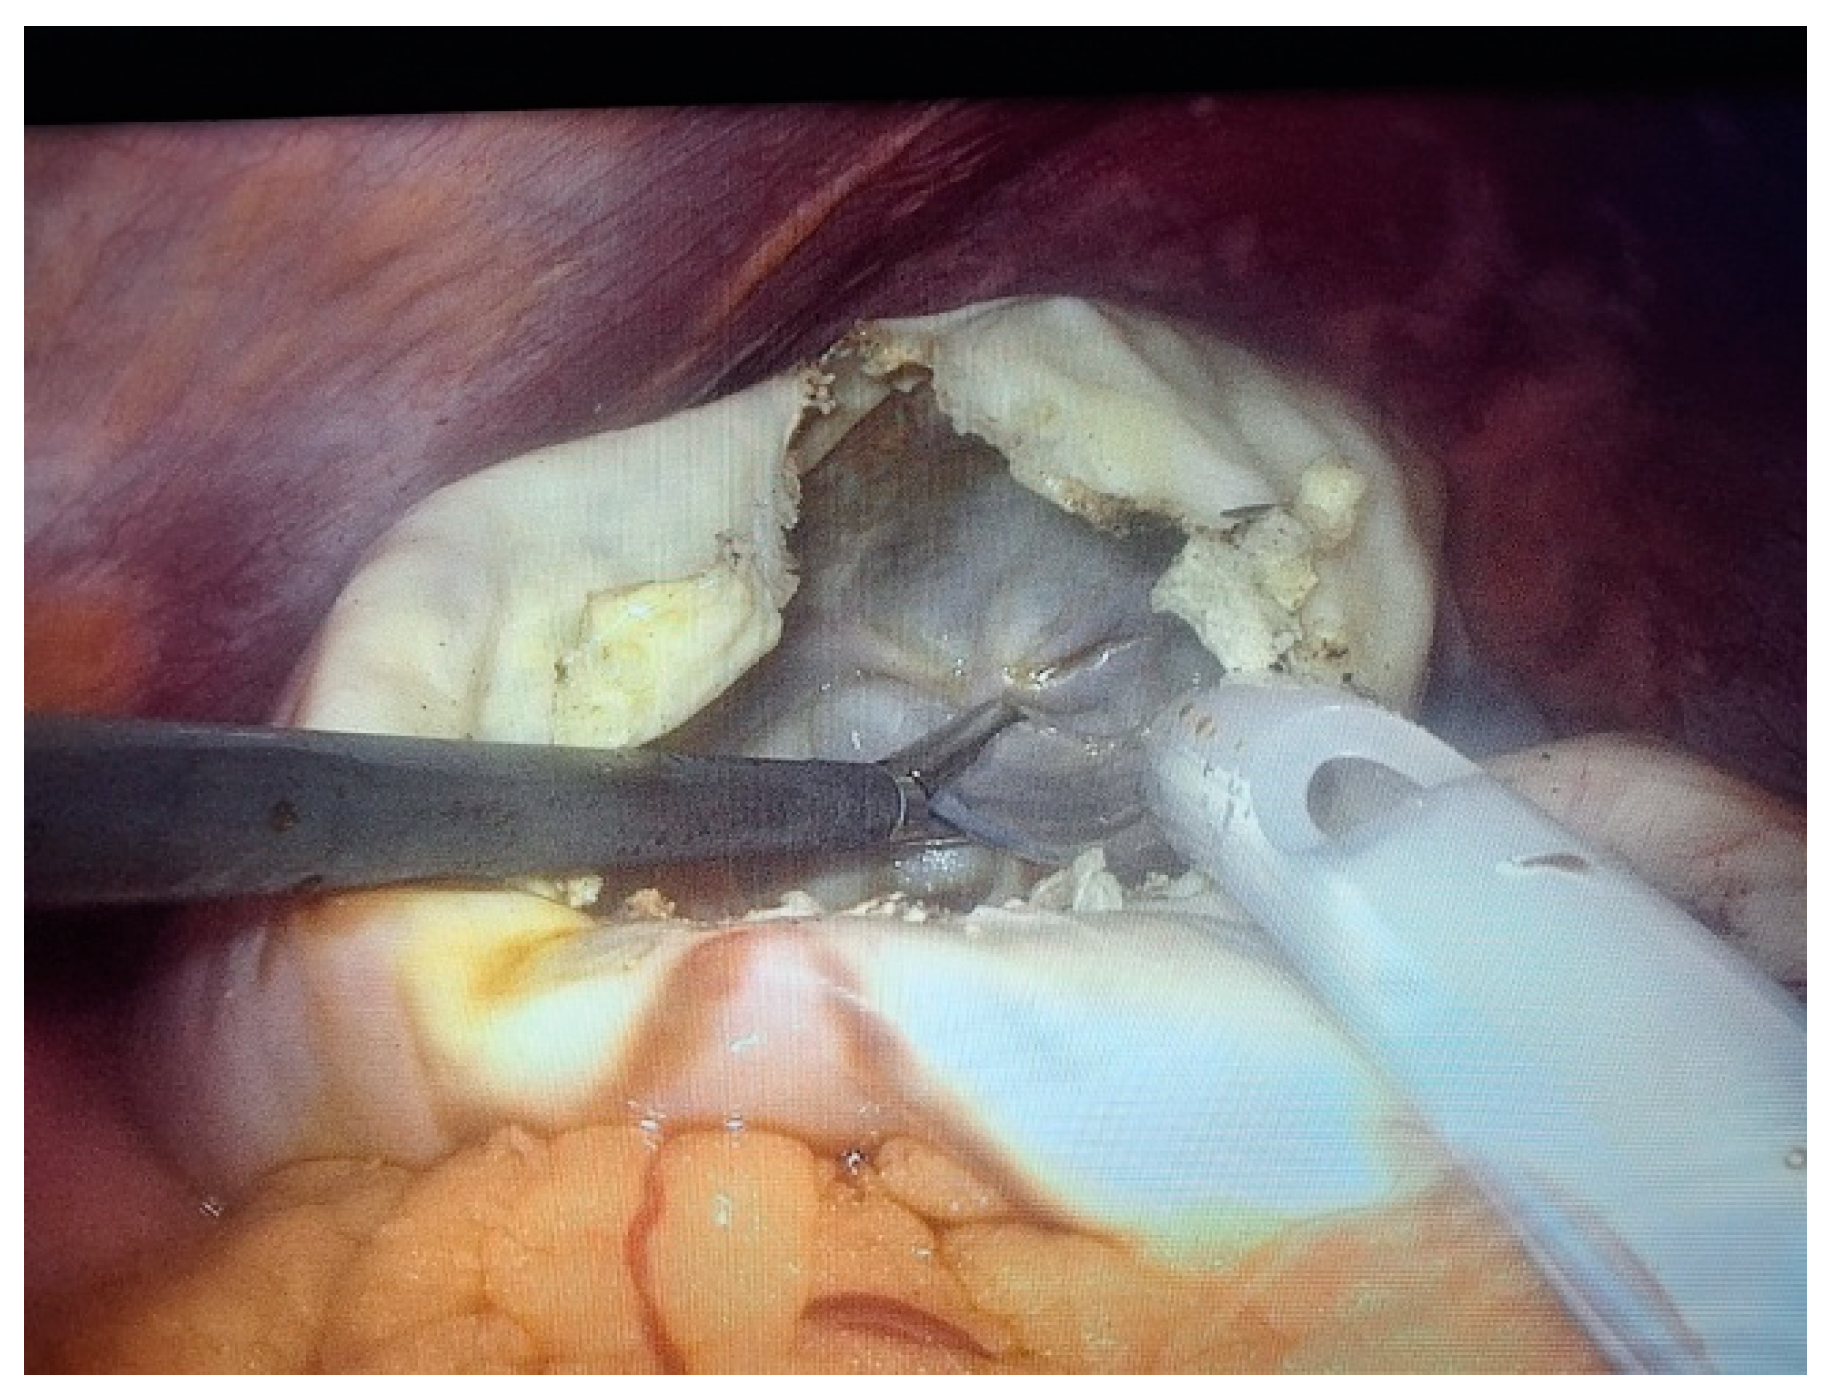

2. Case Presentation

- Grade I splenomegaly with simple voluminous splenic cyst, 10 cm in diameter.

- Accessory spleen adjacent to the lower pole of the spleen.